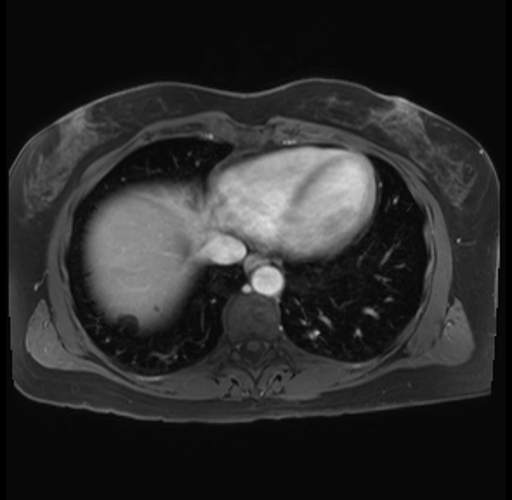

Imaging Analysis

Look through the patient's CT scan to identify any areas of concern for the necessary procedure.

Based on your CT findings, which issue(s) are present and would give reason for "planned slowing down moment(s)" in this case?